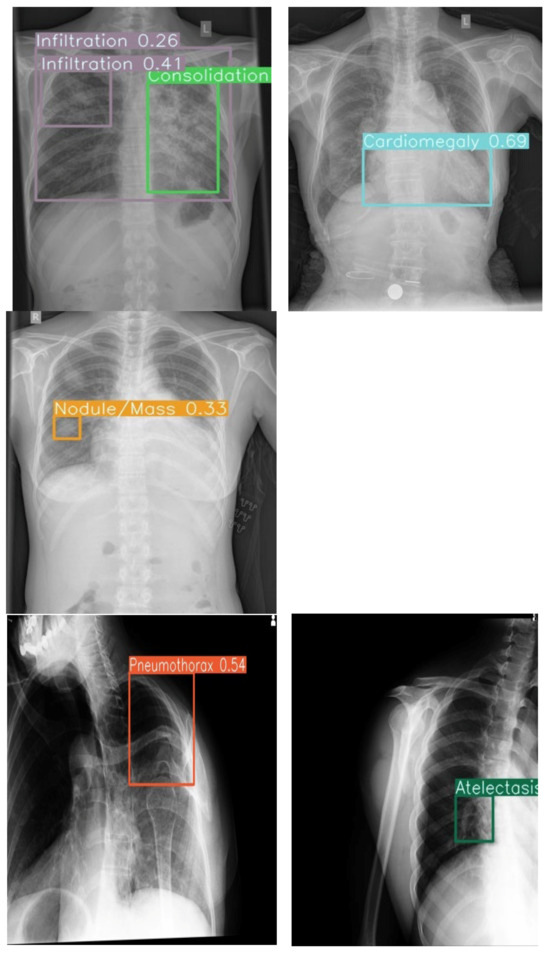

Diagnostic Accuracy of an Offline CNN Framework Utilizing Multi-View Chest X-Rays for Screening 14 Co-Occurring Communicable and Non-Communicable Diseases

Background: Chest radiography is the most widely used diagnostic imaging modality globally, yet its interpretation is hindered by a critical shortage of radiologists, especially in low- and middle-income countries (LMICs). The interpretation is both time-consuming and error-prone in high-volume settings. Artificial Intelligence (AI) [...] Read more.

Background: Chest radiography is the most widely used diagnostic imaging modality globally, yet its interpretation is hindered by a critical shortage of radiologists, especially in low- and middle-income countries (LMICs). The interpretation is both time-consuming and error-prone in high-volume settings. Artificial Intelligence (AI) systems trained on public data may lack generalizability to multi-view, real-world, local images. Deep learning tools have the potential to augment radiologists by providing real-time decision support by overcoming these. Objective: We evaluated the diagnostic accuracy of a deep learning-based convolutional neural network (CNN) trained on multi-view, hybrid (public and local datasets) for detecting thoracic abnormalities in chest radiographs of adults presenting to a tertiary hospital, operating in offline mode. Methodology: A CNN was pretrained on public datasets (Vin Big, NIH) and fine-tuned on a local dataset from a Nepalese tertiary hospital, comprising frontal (PA/AP) and lateral views from emergency, ICU, and outpatient settings. The dataset was annotated by three radiologists for 14 pathologies. Data augmentation simulated poor-quality images and artifacts. Performance was evaluated on a held-out test set (N = 522) against radiologists’ consensus, measuring AUC, sensitivity, specificity, mean average precision (mAP), and reporting time. Deployment feasibility was tested via PACS integration and standalone offline mode. Results: The CNN achieved an overall AUC of 0.86 across 14 abnormalities, with 68% sensitivity, 99% specificity, and 0.93 mAP. Colored bounding boxes improved clarity when multiple pathologies co-occurred (e.g., cardiomegaly with effusion). The system performed effectively on PA, AP, and lateral views, including poor-quality ER/ICU images. Deployment testing confirmed seamless PACS integration and offline functionality. Conclusions: The CNN trained on adult CXRs performed reliably in detecting key thoracic findings across varied clinical settings. Its robustness to image quality, integration of multiple views and visualization capabilities suggest it could serve as a useful aid for triage and diagnosis. Full article

Show Figures

Figure 1